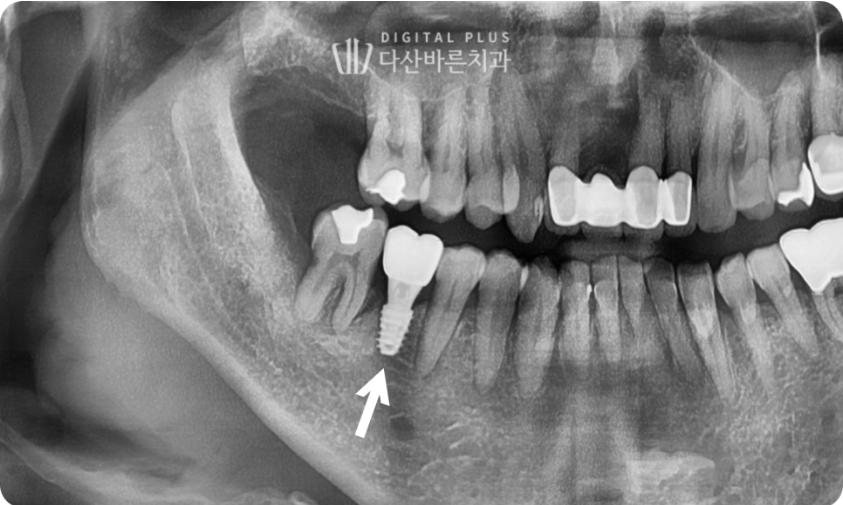

▲ 교정으로 형성된 공간에 임플란트 식립 후 무너진 치아 배열과 교합을 회복한 모습.

<최종 치료 전후 사진>